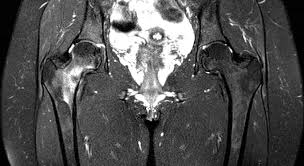

Medications for Stress Fractures You can take over-the-counter medications to manage pain. Initial treatment of a hip stress fracture may include X-rays a magnetic resonance imaging MRI scan or a bone scan to further evaluate your condition.

Coronal Mri T1w Image Showing The Stress Fracture As Linear Download Scientific Diagram